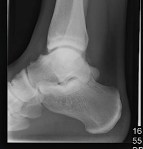

Some patients also have pain at the front of the ankle when they walk, caused by spurring at the front of the ankle joint. Ankle arthroscopy can be useful to remove this spur, and improve patient’s pain when walking.